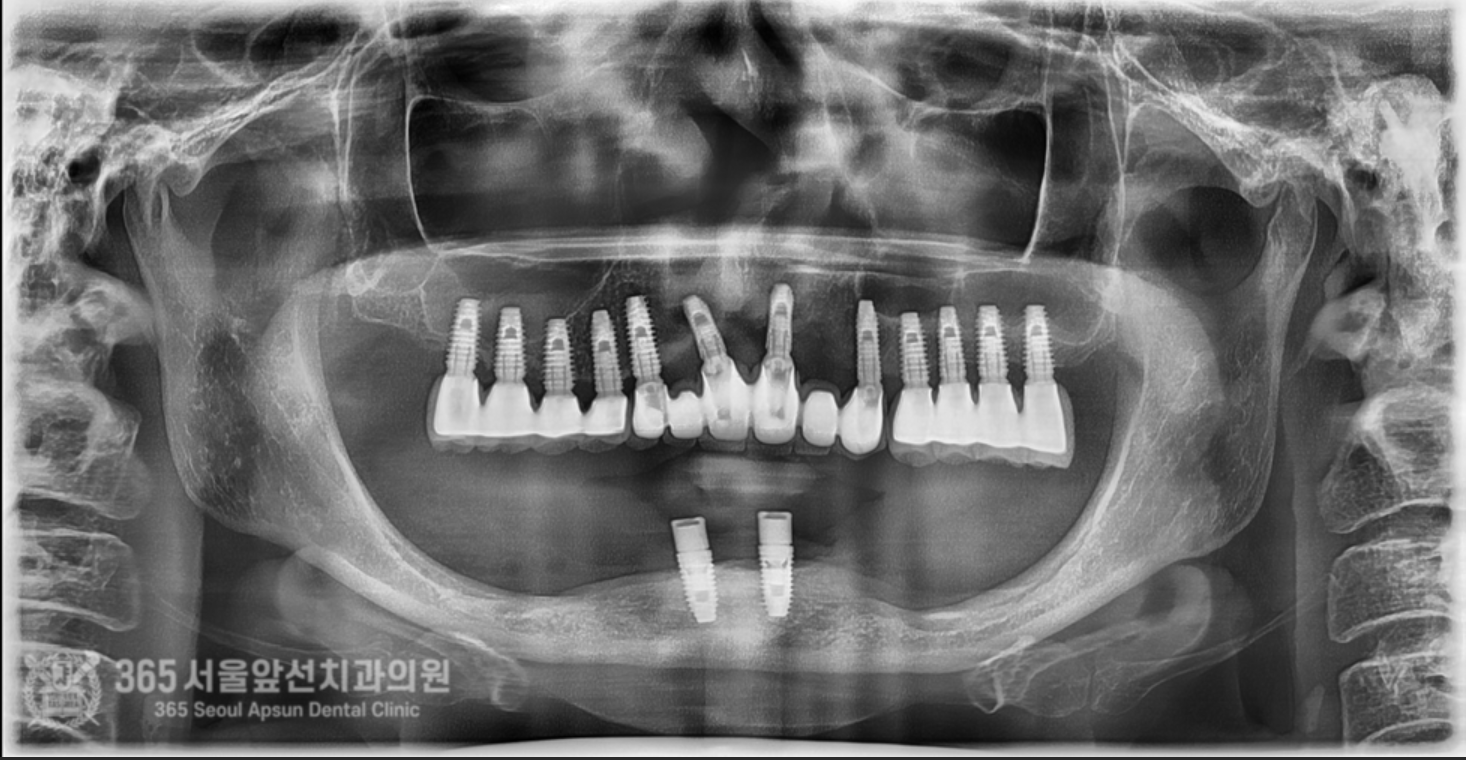

아래쪽에 임플란트 틀니를 썼었는데, 전체 임플란트 치료를 받고 싶어서 치과에 갔더니 뼈가 없어서 임플란트가 불가능하다고 판정받았어요. 촬영일시 : 2024.07.07. 처음 내원 당시 엑스레이 사진입니다. 촬영일시 : 2024.07.07. 사진에 노란색 표시를 한 곳이 신경관입니다. 보다시피 어금니 부위에는 뼈가 하나도 없습니다. 이 정도 뼈 상태라면 1000명의 환자분이 오신다면 그 중 단연코 1등으로 뼈가 안좋으신 상태 정도 됩니다. 기존의 임플란트는 제거를 해야하고, 이후 신경관을 피해서 5개의 임플란트를 식립하기로 했습니다. 촬영일시 : 2024.07.07. 수술 전 CT 사진으로 신경 구조물에 대한 정확한 사전 파악 후 수술에 들어갑니다. 왼쪽 아래턱 부위의 신경이 손상되지 않게 조심스럽게 수술을 진행했습니다. 오른쪽 아래턱 부위도 동일하게 신경이 손상되지 않게 조심스럽게 수술을 진행합니다. 기존 임플란트는 상태가 좋지 않아서 제거했습니다. 촬영일시 : 2024.07.07. 촬영일시 : 2024.11.16. 임플란트 수술 후 엑스레이입니다. 원하는 위치에 정확히 임플란트가 식립되었습니다. 임플란트가 뼈와 단단하게 굳으면 본을 떠줍니다. 정교한 보철물을 위해선 정확한 본뜨기 작업은 필수겠죠? 촬영일시 : 2024.11.16. 완성된 보철물입니다. 촬영일시 : 2024.11.16. 대략 4개월에 걸쳐 치료를 완료해드렸습니다. 환자분께서는 아주 만족하셨습니다. 정확한 임플란트 수술을 통해 신경 손상없이 성공적으로 마무리할 수 있었습니다 ㅎㅎ 촬영일시 : 2024.07.07. / 2024.11.16. 보철물 장착 전후의 입술 모습의 변화를 볼 수 있습니다. 입술이 볼록하게 지지받아서 자연스러운 안모로 변화했습니다. 촬영일시 : 2024.07.07. / 2024.11.16. 전후 구강내 사진입니다. 잇몸뼈가 많이 없으셔서 잇몸 부위를 핑크색이 나는 재질로 채워드렸습니다. 임플란트 불가능 판정을 받으셨던 환자분이신데 치료가 잘 마무리 되어 뿌듯했습니다 ㅎㅎ 신경관이 근접한 고난이도 임플란트 치료지만 충분한 경험과 지식이 있다면 치료가 가능하니 걱정 안하셔도 되겠습니다. 지금까지 365일 열린 가까운 서울대학교 치과병원을 지향하는 365서울앞선치과였습니다. 감사합니다. [ 치료기간 : 2024년 7월7일 ~ 2024년 11월 16일 ] ※ 365서울앞선치과의원의 모든 포스팅은 각 진료과 의료진이 직접 작성합니다. 365서울앞선치과의원 블로그의 임상 케이스 게시물은 환자분께 의학적으로 정확하고 상세한 정보를 드리기 위해 각 진료과 의료진이 직접 작성하며, 모든 증례 사진은 본원 의료진이 직접 시술한 증례를 촬영한 것으로, 의료법 제23조, 제56조에 의거하며 환자분의 동의를 얻어 포스팅에 사용하였습니다. 또한 해당 케이스는 본 환자분의 치료 결과이며, 환자 상태에 따라 치료의 결과는 달라질 수 있습니다. |